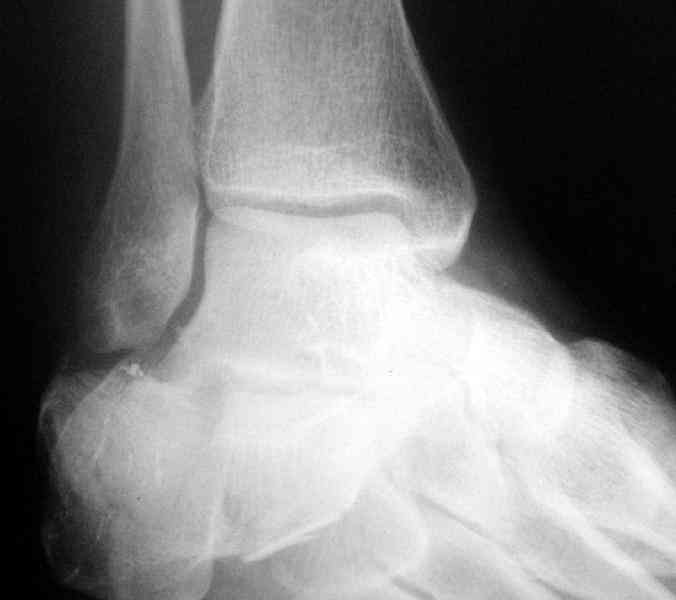

Re: Перелом пяточной кости

Открытый и закрытый способы лечения.